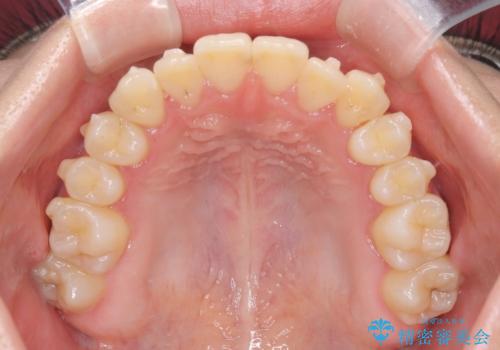

診査の結果、すでに下顎前歯の抜歯が行われていましたが、マウスピースの適合が著しく悪くなっており、歯が計画通りに動いていない状態でした。また、歯を支える骨の厚みや歯肉の薄さを考慮すると、このままマウスピースによる傾斜移動を続けるのは歯肉退縮(歯茎が下がること)のリスクが非常に高いと判断。

装置の変更と歯肉への配慮: ワイヤー矯正は歯の根(歯根)を平行に移動させる「歯体移動」を得意としています。本症例では、歯肉退縮を防ぐために、歯の傾きを精密にコントロールしながら抜歯スペースを閉じる必要がありました。ワイヤー装置を用いることで、インビザラインでは難しくなっていた三次元的な細かい調整を可能にしました。